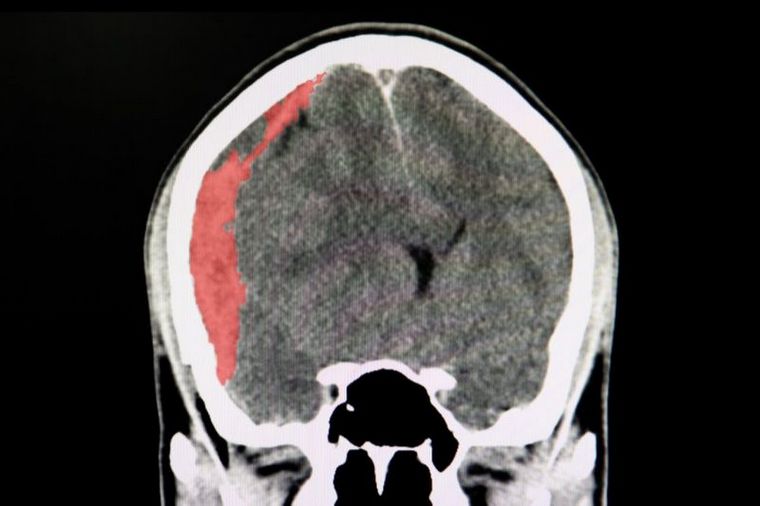

Qué es un hematoma subdural, motivo de operación a Maradona

Se trata de una pequeña acumulación de sangre entre las membranas que recubren el cerebro. Puede producirse por traumatismos o consumo de medicamentos anticoagulantes. La explicación de especialistas.

El director médico de Hospital Privado, Ricardo Pickesteiner (MP 23062/5), explicó a Cadena 3 que los hematomas cerebrales generalmente no revisten mayor gravedad.

“La ruptura o sangrado de una de las venas de la membrana de la duramadre es provocada por traumatismos o traumatismos banales de cráneo cefálicos”, señaló.

Inicialmente no general síntomas, ya que el sangrado o la producción de este hematoma se generan muy lentamente, y la aparición de síntomas precisos son tardíos.

“Son frecuenten también en pacientes que toman anticoagulantes o antiagregantes, como las aspirinas o anticoagulantes por arritmia”, ejemplificó.

Generalmente no revisten gravedad, salvo que estén localizadas en lugares que produzcan síntomas importantes y se requiere una intervención quirúrgica. “De lo contrario, la gran mayoría de los casos sólo necesitan observación y control”, concluyó Pickesteiner.

Por su parte, el jefe del servicio de Neurología del Instituto Modelo de Cardiología, Daniel Velázquez (MP: 24808), explicó a Cadena 3 que el hematoma puede ser agudo (reciente, con pocos días de evolución), subagudo (con varios días) o crónico.

“No sangran permanentemente, sino que sangra y se produce una membrana alrededor del hematoma, que atrae líquido a su interior. Es una membrana semipermeable que permite que entre líquido pero no que salga, por eso aumenta su tamaño”, especificó.

El especialista apuntó que en ocasiones se detecta porque genera problemas para caminar, ubicarse y hasta “cuadros de demencia”, porque el paciente empieza a perderse o a perder funciones motoras.

Por la evolución de Maradona, consideró que parece ser un cuadro subagudo o crónico, donde el procedimiento “no es tan invasivo porque la sangre es espesa”. Aclaró en ese sentido que es una cirugía que no es de alta complicación, pero que hay que tomar los recaudos adecuados. En general, la recuperación suele ser buena y rápida.

El astro Diego Armando Maradona, actual entrenador de Gimnasia, deberá ser operado de un hematoma subdural en la cabeza luego de los estudios que se le realizaron en una clínica de la ciudad bonaerense de La Plata.